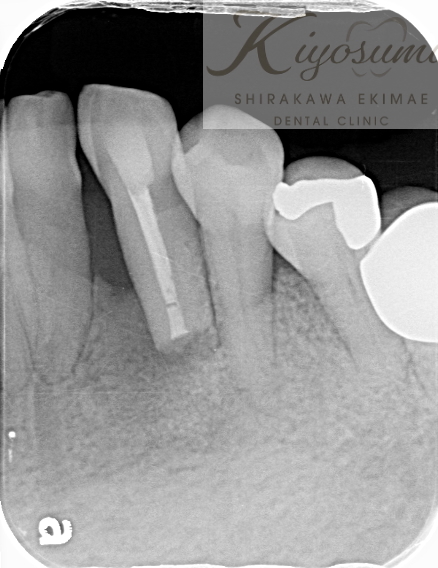

| 主訴 | 歯が揺れて噛めないので、噛めるようにして欲しい。 |

| 治療内容 | 基本的な歯周病治療、根の治療を実施し、歯の高さが足りない箇所は歯冠長延長術、保存が難しい歯は一部歯根分割抜去を行いました。欠損部はインプラントを用いず、ジルコニアブリッジで仕上げています。 |

| 想定されたリスク | ※残存している歯の本数が少ないため、残っている歯だけでブリッジを行うには長期予後が見込めない可能性があり、患者さんにご理解をいただいたうえで被せ物を行っています。 ※歯周病治療や根の治療をしても歯を残せない可能性がありました。 |